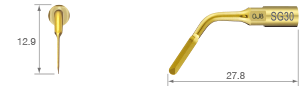

TiN coating / Triple sided edge spatula tip

TiN coating / Edge spatula tip

TiN coating / Rounded edge spatula tip

For chin bone harvests, notably for the mental foramen and mandibular ramus. For general bone surgery.

• POWER LEVEL [SURG] 100%

• TiN coating

• Dots mark 6, 8 and 10 mm from tip end

• 18 teeth ; 0.35 mm thick